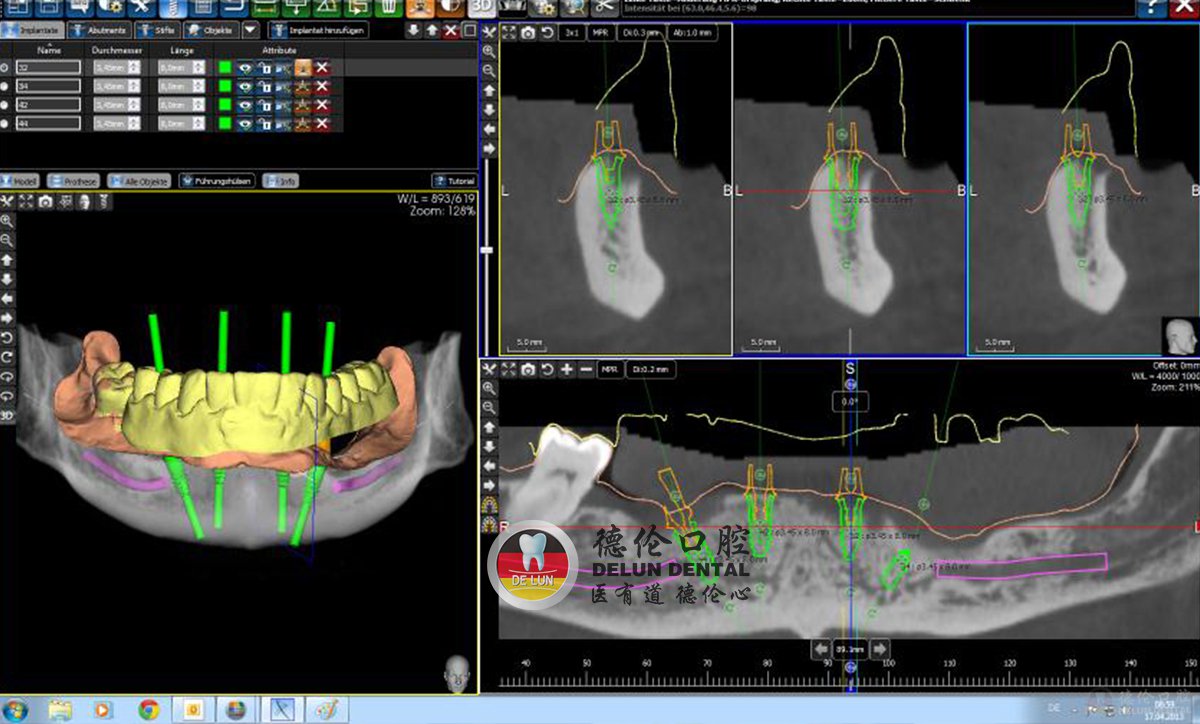

2015年,德伦口腔引进德国数字化3D导板种植,成为华南区首家拥有该技术的医疗机构。

术前:通过CBCT获取患者口腔信息,重建口腔三维模型,通过模拟种牙过程,有效避开神经等重要解剖位置,减少创伤优化种植方案。

术中:利用设计打印的3D种植导板,医生在导板的辅助下准确有效把握整个种植过程。

术后:患者可以享受到微创、准确、舒适的新数字化种植体验。